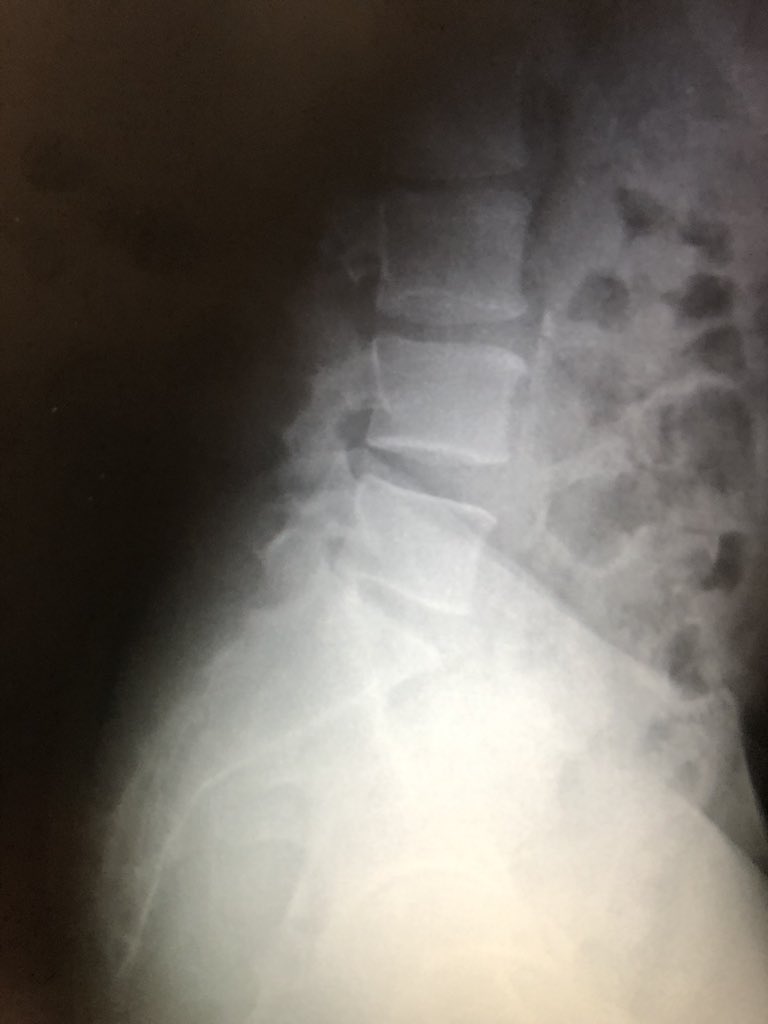

Posterior fixation and fusion at the L4-L5 level. | Download Scientific

WebForo de Artrodesis Lumbar. Foro para debatir sobre cualquier tema relacionado con la Artrodesis Lumbar. Más información sobre Traumatología y Cirugía Ortopédica en. WebEn el caso de la artrodesis lumbar, los niveles fusionados suelen ser L4-L5 y L5-S1. Esta es una operación que idealmente debe ser utilizada como último recurso, después de pasar. WebCodigo:TM112 hasta un 30% en https://www.zumub.com/ES/Codigo:TM112 un 25% enhttps://serenitycbd.es/collections/aceites WebLa artrodesis lumbar es una intervención quirúrgica en la cual se fusionan dos vértebras de la la espina dorsal a nivel lumbar con el fin de ajustar su posición,. WebTengo 22 años y estoy operada desde hace año y medio de artrodesis lumbar posterior con tornillos y fijación desde L4 L5 S1 no puedo realizar muchos. WebArtrodesis lumbar l4-l5-s1 secuelas Fusión de L4 a s1 Aunque las fusiones espinales multinivel son un procedimiento común y necesario para tratar muchos tipos de. WebLa resonancia dejaba clara la razón de esos dolores: dos protusiones entre las vertebras lumbares l4-l5 y la l5-s1 que ademas ya empezaban a apretar los nervios ciáticos. Foto.

WebArtrodesis lumbar l4-l5-s1 secuelas Fusión de L4 a s1 Aunque las fusiones espinales multinivel son un procedimiento común y necesario para tratar muchos tipos de. WebLa resonancia dejaba clara la razón de esos dolores: dos protusiones entre las vertebras lumbares l4-l5 y la l5-s1 que ademas ya empezaban a apretar los nervios ciáticos. Foto. WebTengo 42 años y soy y paciente operado en 2013 con fusión mediante barras y tornillos de L4, L5 y S1. Actualmente los Dolores y la impotencia funcional me.